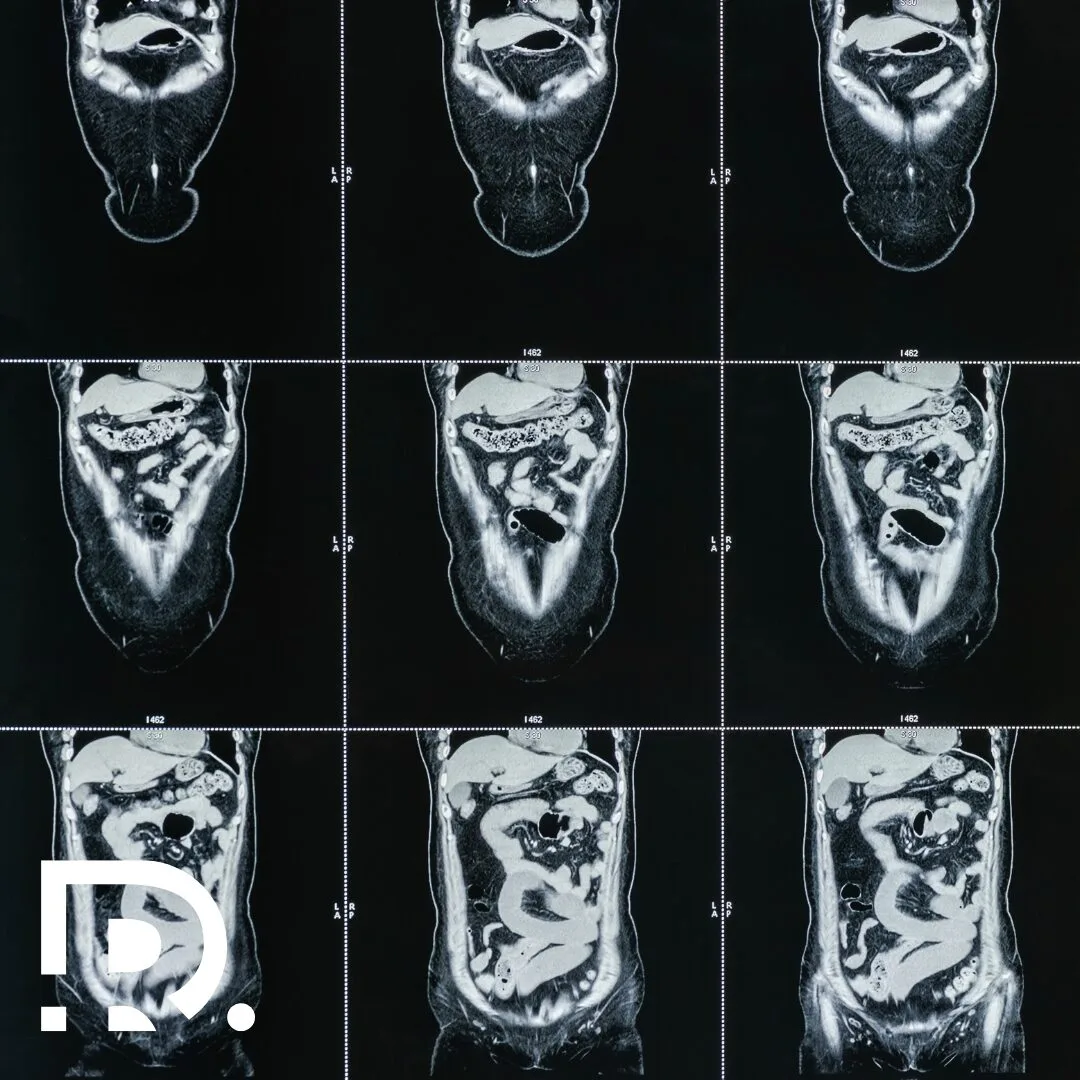

Cel mai frecvent, acestea sunt evidențiate prin:

- ecografie abdominală;

- tomografie computerizată (CT);

- rezonanță magnetică (RMN);

- investigații imagistice de screening.